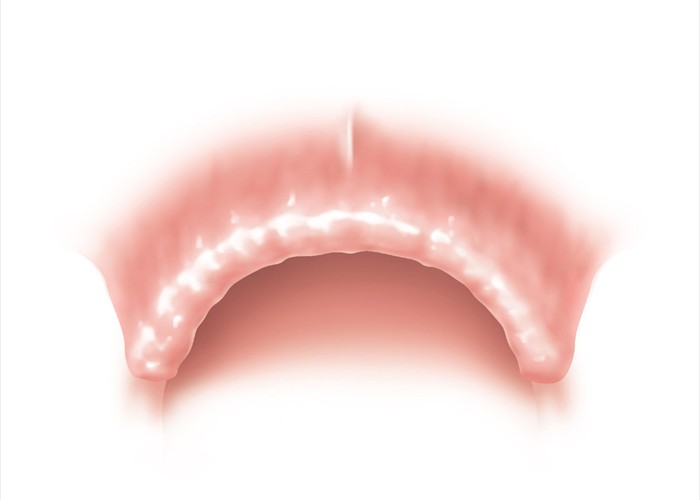

Einbringen von 6 Implantaten für eine festsitzende Versorgung

Einbringen von 6 Implantaten für eine festsitzende Versorgung